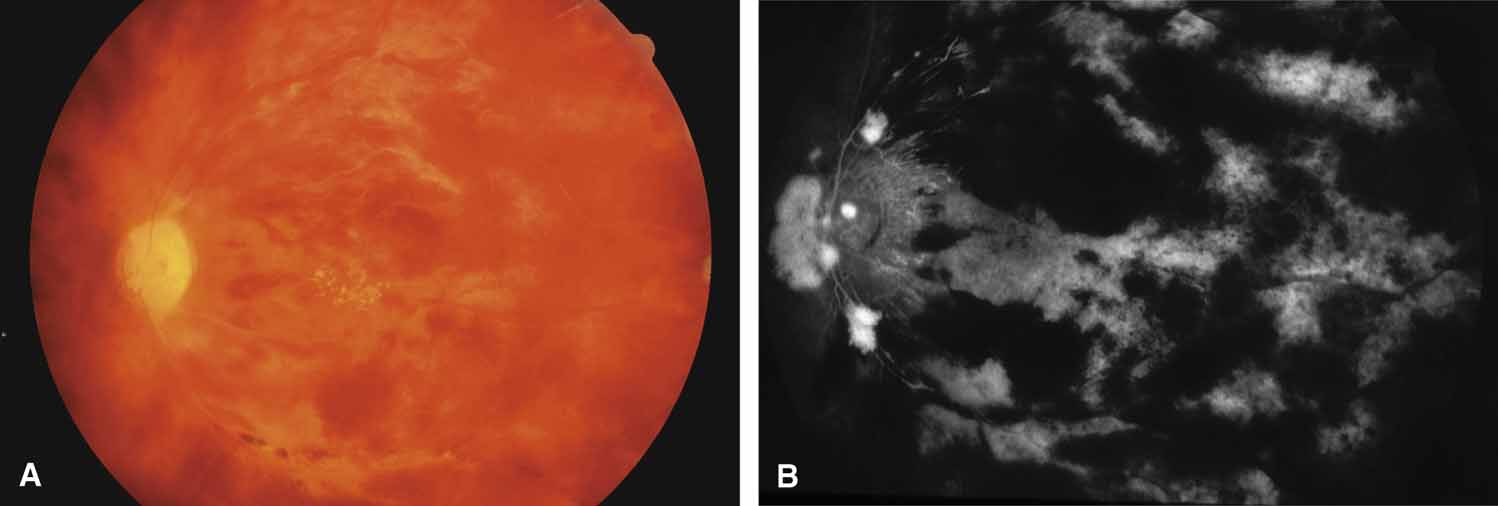

Carotid Artery Disease

Features of ocular ischemia including neovascular glaucoma may develop when severe carotid occlusive disease results in hypoperfusion. A dot-blot peripheral retinopathy with microaneurysms (venous stasis retinopathy of Kearns) may be present in 5% of patients with established carotid artery stenosis of greater than 70% flow reduction (Fig. 26). However, iris neovascularization and glaucoma may develop in the absence of posterior segment manifestations148 and make the underlying carotid pathology difficult to diagnose. Since the ciliary body is subject to both hypoxia and hypoperfusion, neovascular glaucoma may be normotensive or even hypotensive.149 Endarterectomy may improve flow and may transiently lead to regression of iris neovascularization and lowering of pressure elevation. When neovascularization of the angle results in increased intraocular pressure, then panretinal photocoagulation is indicated. Other cycloablative methods, such as transscleral diode laser cyclophotocoagulation therapy or continuous wave transscleral Nd: YAG ablation, may be considered when panretinal photocoagulation fails or is not possible.

Fig. 26 Venous stasis retinopathy of carotid artery disease. A. Mid-peripheral dot-blot hemorrhages and microaneurysms in asymptomatic patient with right carotid obstruction. B. Digital subtraction angiogram, venous method, showing complete right internal carotid obstruction (Ic) (v, vertebral; Ic, internal carotid; Rc, right common carotid; Lc, left common carotid).